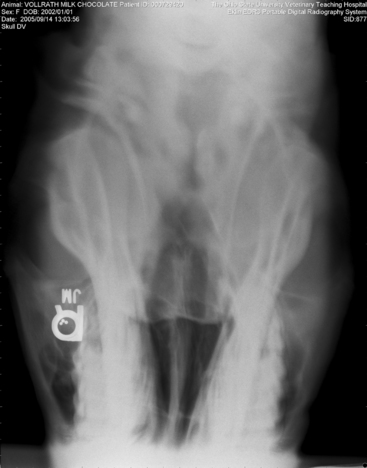

Figure 22-17 Motion artifact. Blurring of this dorsoventral image of a horse skull was caused by head movement during the radiographic exposure. Note that the “R” marker is not blurred; this is because the leaded marker has been placed on the stationary image detector.